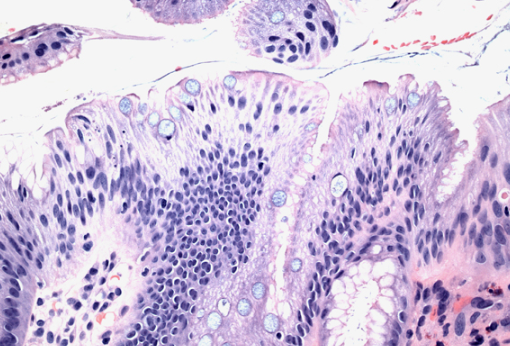

장상피화생은 위 점막이 장 점막처럼 바뀌는 현상입니다. 위 점막은 본래 산성 환경에서 잘 버틸 수 있도록 구성되어 있지만, 오랜 기간 위염이나 헬리코박터균 등에 의해 자극을 받을 경우 장 세포처럼 변형되기도 합니다. 이는 위의 방어기능이 약해졌다는 신호로 볼 수 있지요.